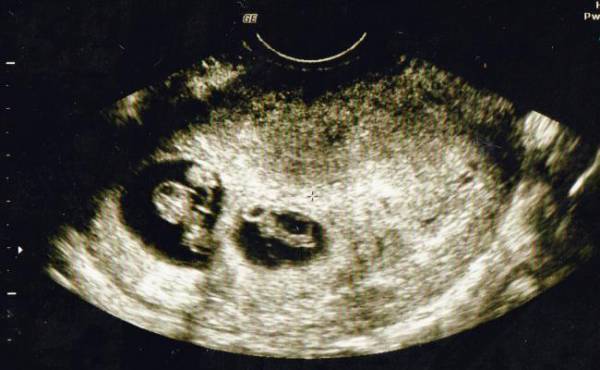

エコーで確認すると3人分の心拍が!

私が3人目を妊娠したのは長男が3歳、次男が1歳のときでした。そろそろ赤ちゃんの心拍が確認できるかな?なんて期待を胸に抱きながら、内診台でエコーを見ていると見覚えのある袋が2つ? その中には心拍のように動いて見えるのが3つ?

私が混乱していると、先生が「お母さん。赤ちゃん何人か見える?」と聞いてきました。先生と一緒に確認し、見事に3人の心拍を確認! パニックで笑うことしかできず、頭の中は真っ白で少しの間その場から動けませんでした。